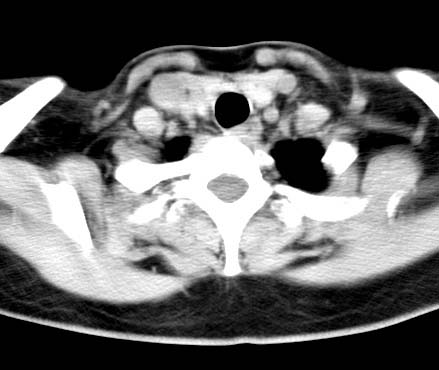

以下是引用sos.la在2008-6-24 5:29:00的发言:[br]可疑项部皮下脂肪肉瘤.穿刺活检.

以下是引用pujunzhi在2008-6-24 7:29:00的发言:[br]后颈部脂肪瘤

以下是引用随光逐影在2008-6-24 7:46:00的发言:[br]考虑项部皮下脂肪瘤或脂肪沉积。